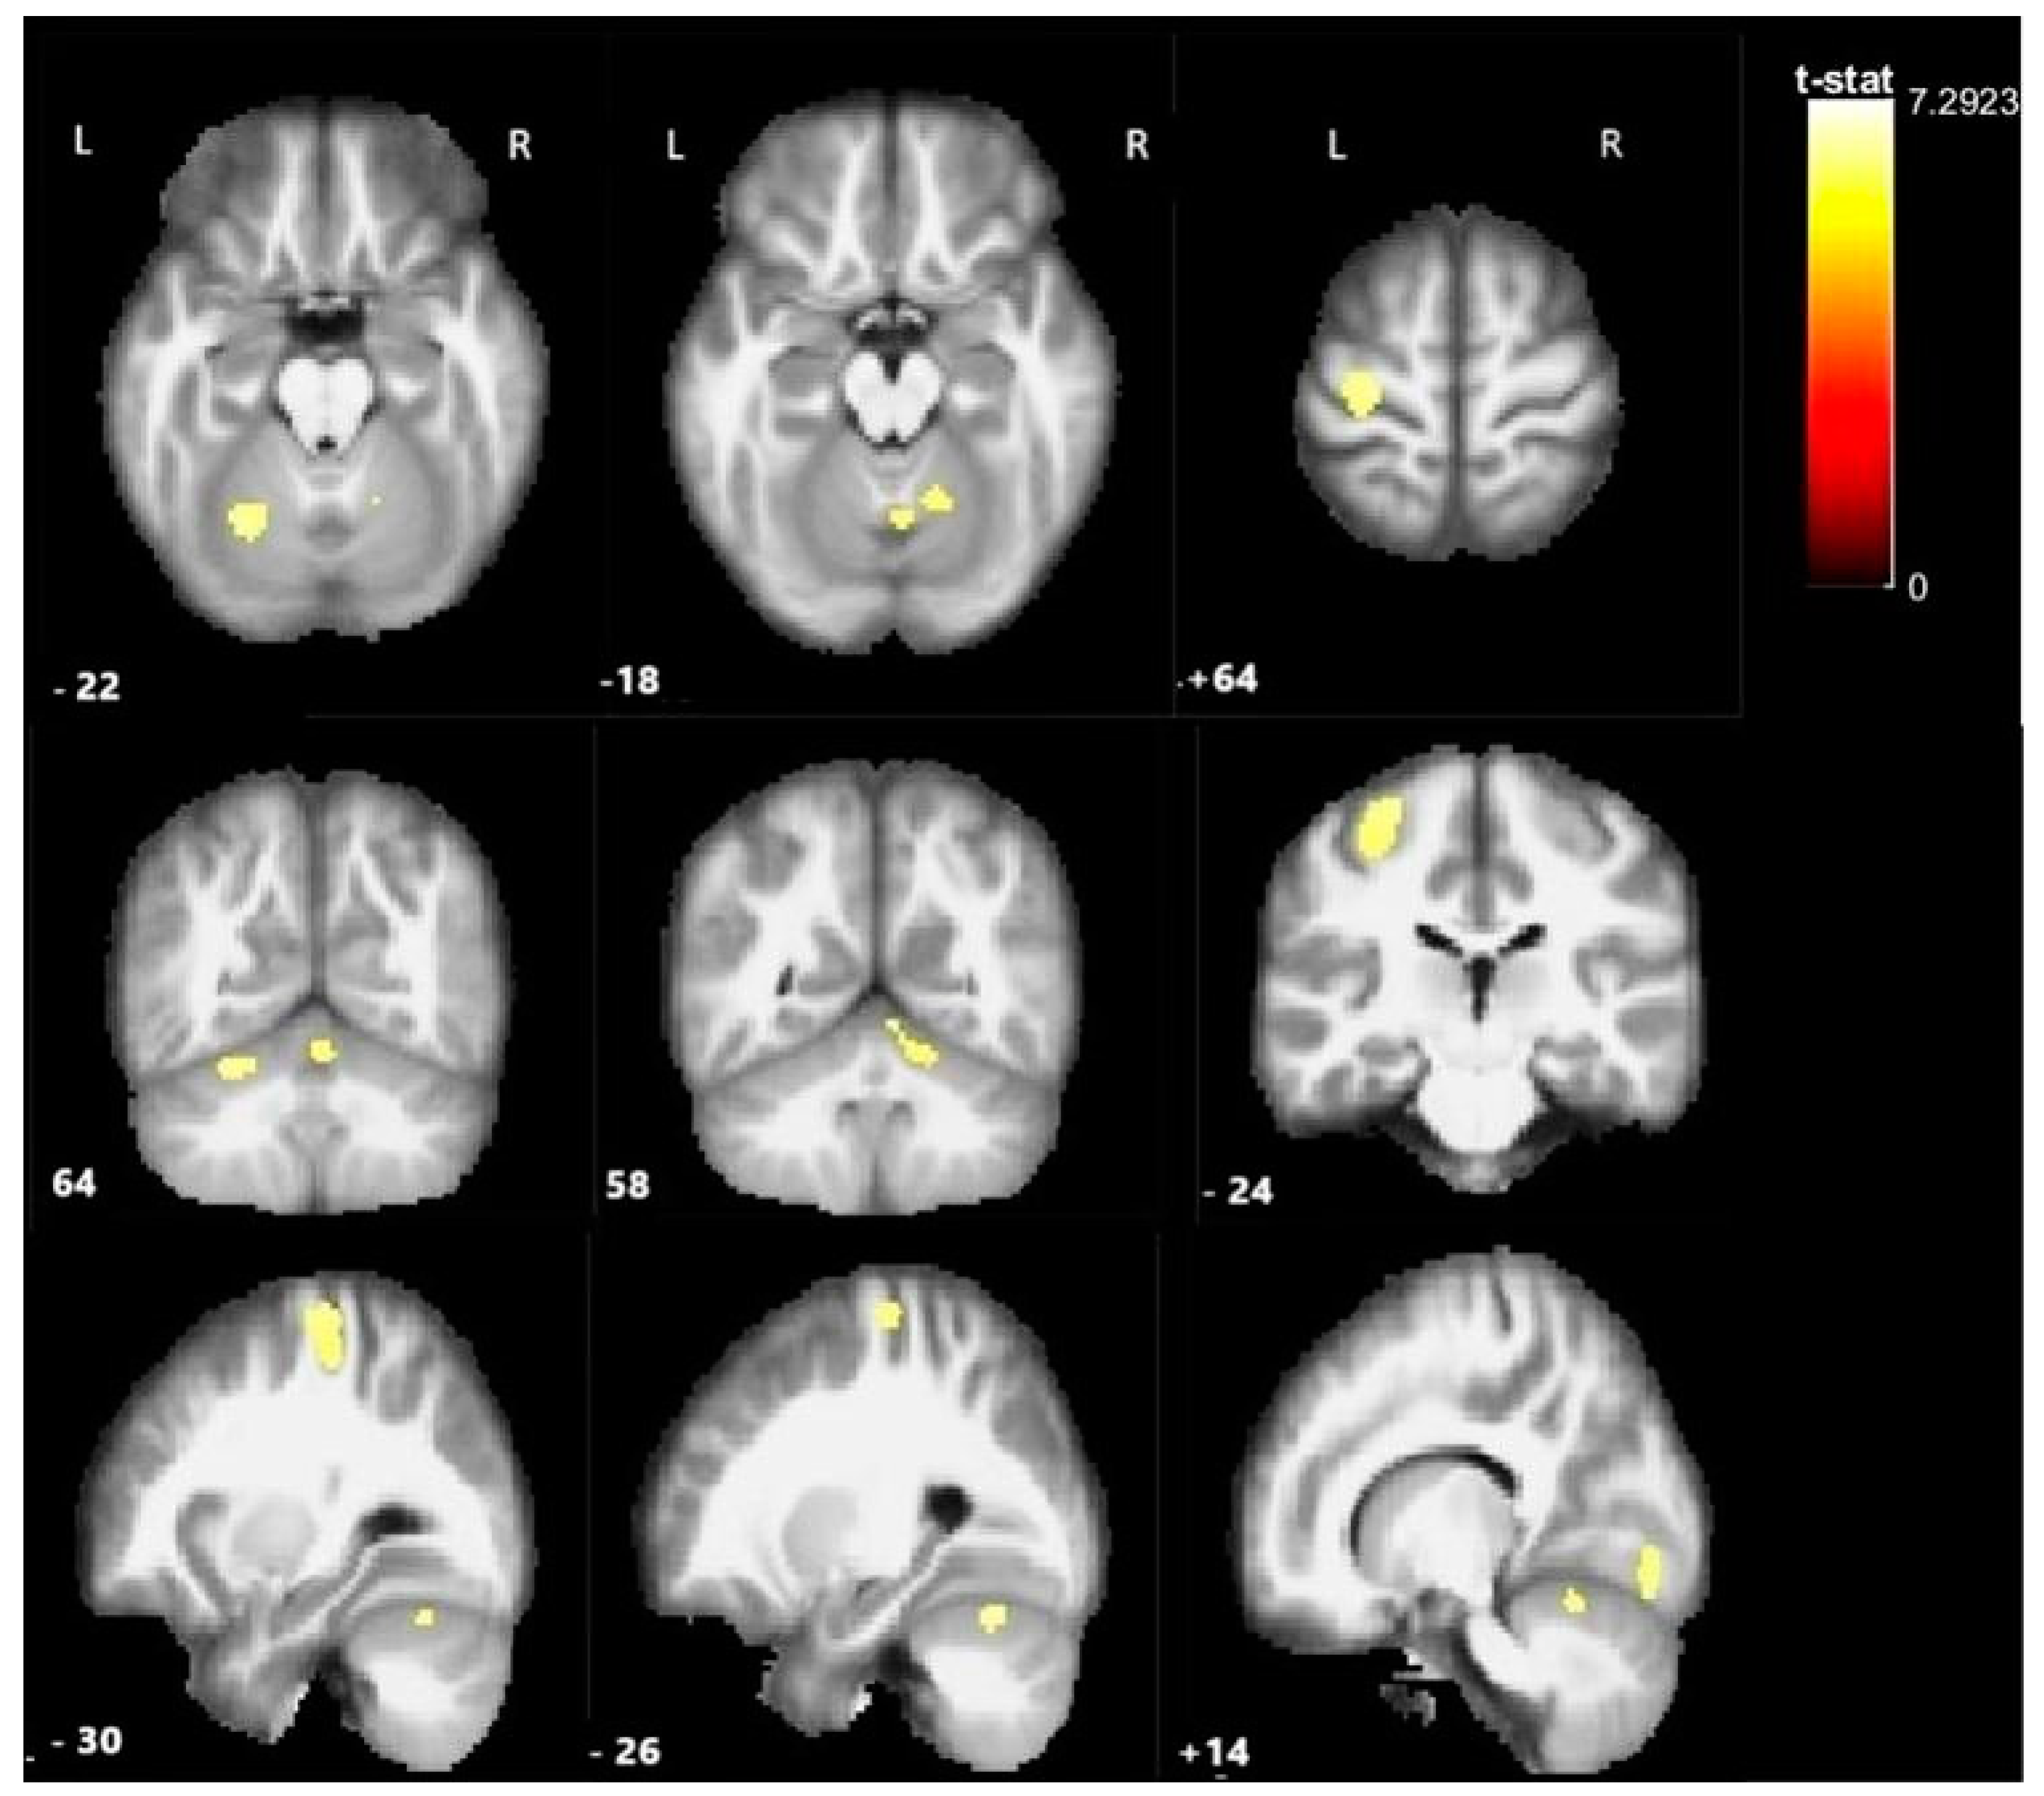

| Activated Clusters | MNI Coordinates | ||||

|---|---|---|---|---|---|

| Region | N Activated Voxels | T-Stat | x | y | z |

| Left precentral gyrus | 426 | 7.300 | −28 | −22 | 66 |

| Left cerebellum (Lobul 1) | 313 | 8.852 | −6 | −84 | −12 |

| Left cerebellum (Lobul VI) | 144 | 7.912 | −26 | −66 | −22 |

| Right cerebellum (Lobul VI) | 188 | 7.003 | 16 | −86 | −14 |

| Cerebellar vermis | 251 | 6.768 | 2 | −64 | −18 |

| Clusters with Significant Activation (Contrast Subcortical > Cortical Lesions) | MNI Coordinates | ||||

| Region | N of Activated Voxels | T-Value | x | y | z |

| Left precentral gyrus | 156 | 5.431 | −34 | −30 | 54 |

| Left postcentral gyrus | 152 | 4.473 | −54 | −22 | 48 |

| Clusters with significant activation (Contrast cortical > subcortical lesions) | MNIcoordinates | ||||

| None | - | - | - | ||